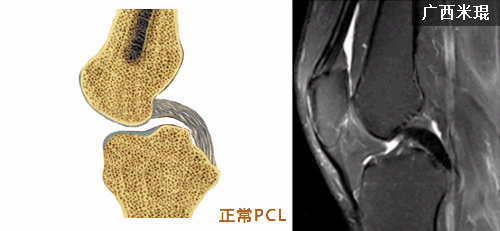

MRI的矢状面是检查后交叉韧带的主要层面,一般无须行胫骨外旋10-15度。

正常后交叉韧带的MRI表现:各序列均为低信号。矢状位韧带为凸面向后的弓形,边缘光滑。

矢状位上弓形的后交叉韧带形成一个135度夹角。

MRI阅片时要注意半月板-股骨韧带对后交叉韧带的影响,其在矢状位后交叉韧带弓形的上下方可见到小的、边缘清晰的低信号影。